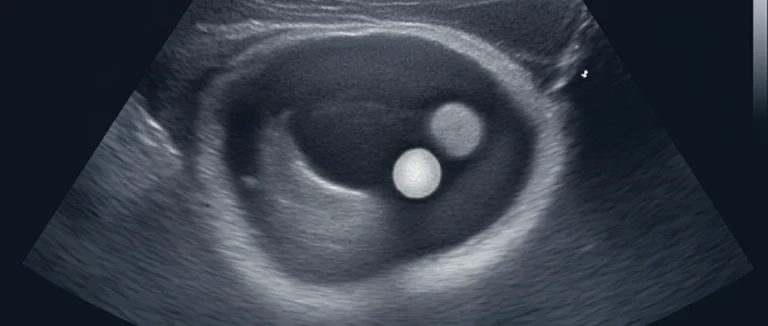

- Подготовка пациента и определение точного положения камня с помощью КТ или УЗИ.

Противопоказания включают беременность, наличие инфекций мочевых путей, неконтролируемую гипертензию, а также определённые анатомические особенности, которые затрудняют точную фокусировку волн. Перед назначением процедуры врач‑нефролог проведёт детальную диагностику, включающую УЗИ, КТ и лабораторные исследования, чтобы оценить возможность успешного лечения.

- Обследование: КТ или УЗИ для точного определения местоположения и размеров камня.